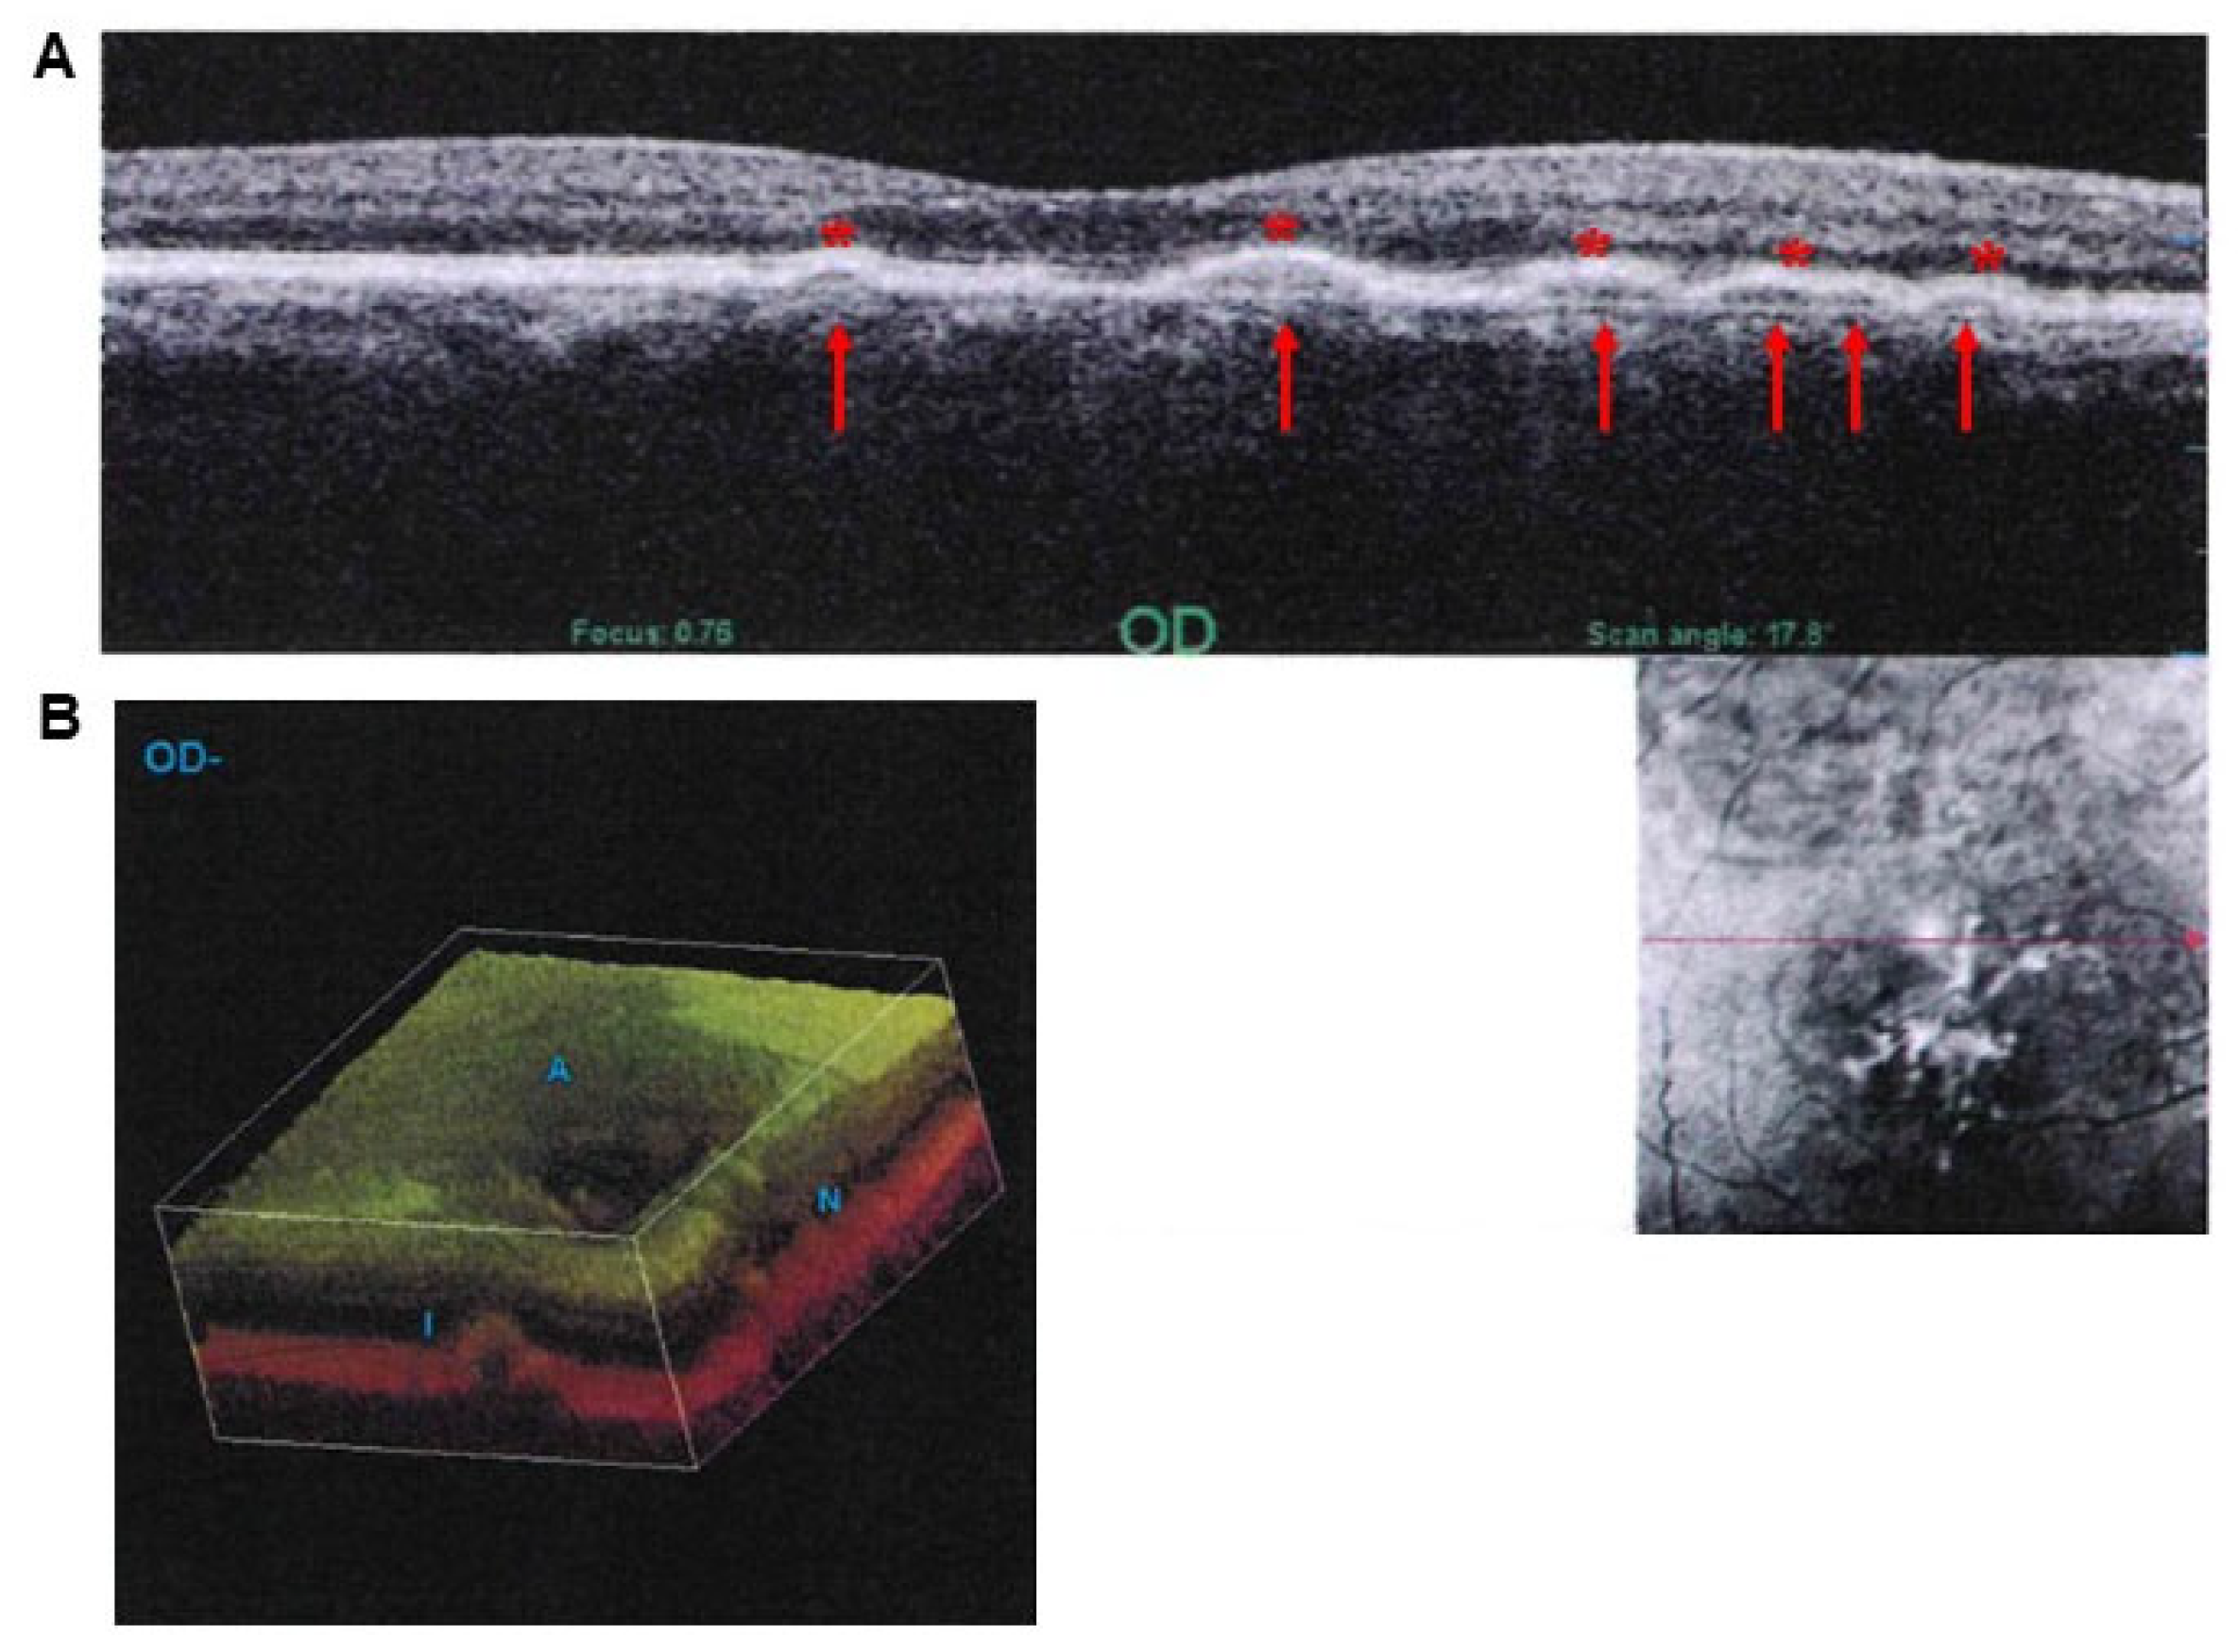

- Pinelli, R.; Bertelli, M.; Scaffidi, E.; Fulceri, F.; Busceti, C.L.; Biagioni, F.; Fornai, F. Measurement of drusen and their correlation with visual symptoms in patients affected by age-related macular degeneration. Arch. Ital. Biol. 2020, 158, 82–104. [Google Scholar] [CrossRef]

- Medical Advisory Secretariat. Optical coherence tomography for age-related macular degeneration and diabetic macular edema: An evidence-based analysis. Ont. Health Technol. Assess. Ser. 2009, 9, 1–22. [Google Scholar]